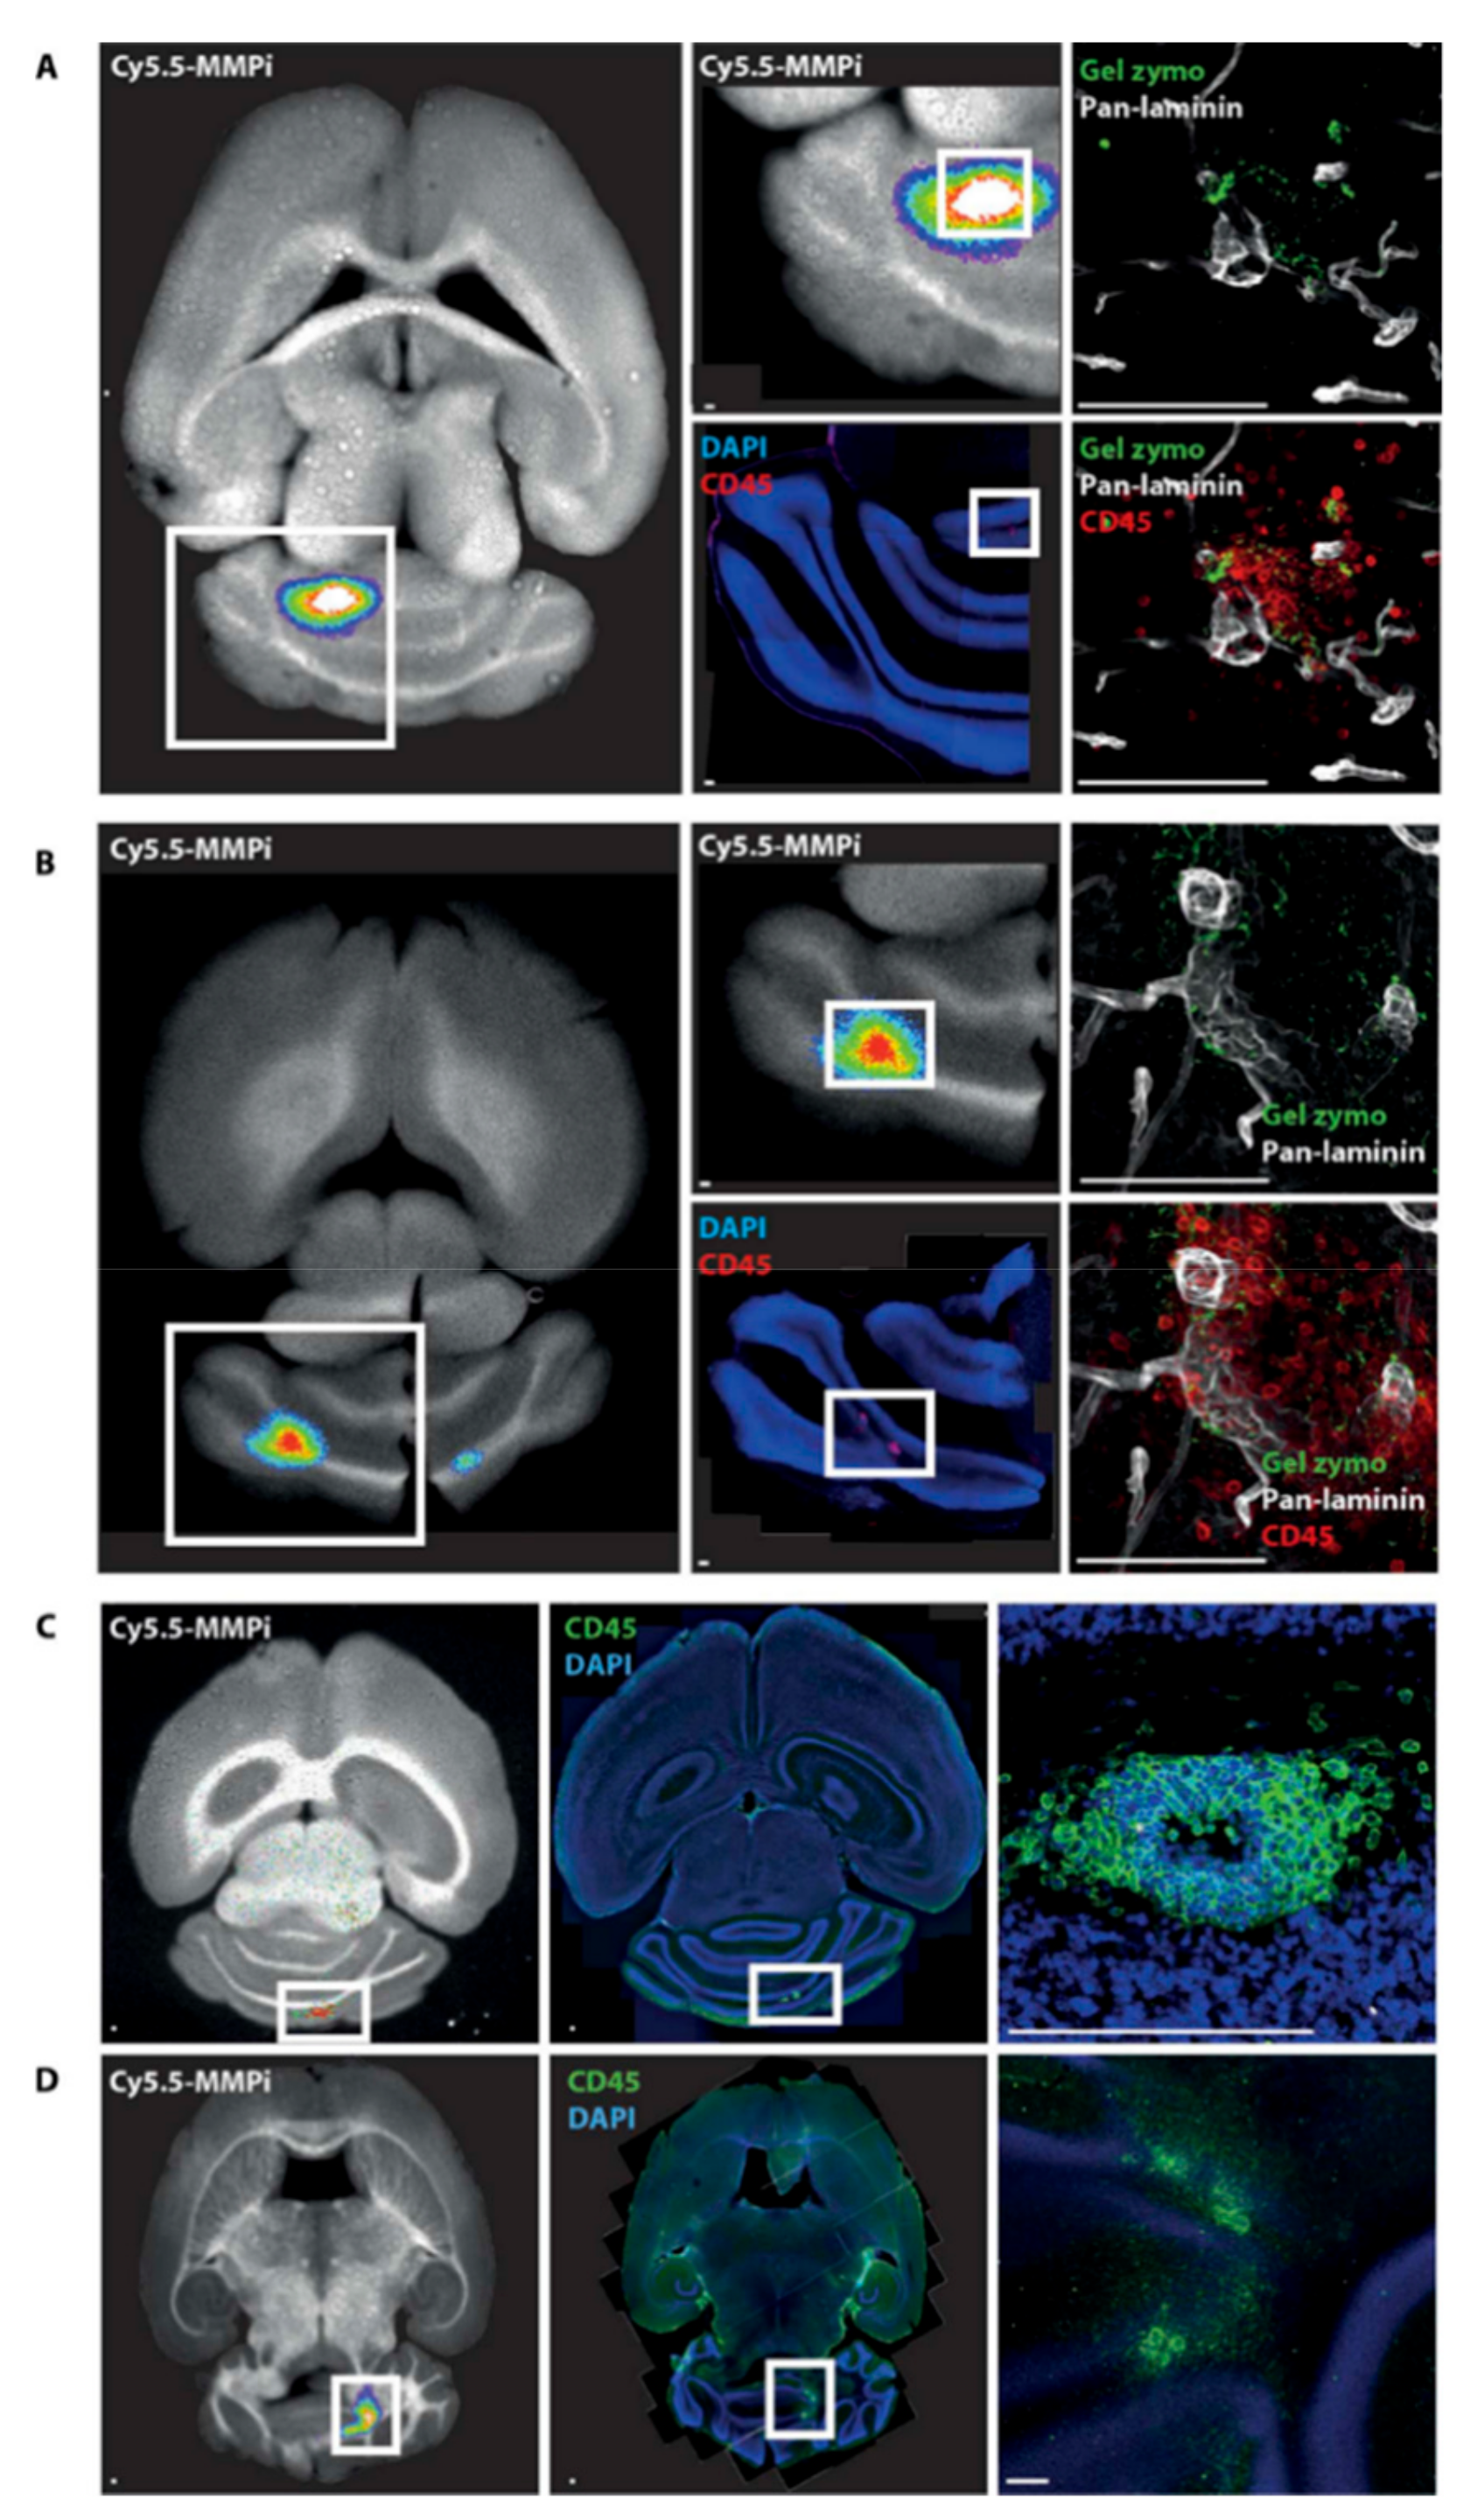

Compound 21 and [18F]15, which were mentioned before as cancer probes, were also studied for EAE and MS. The injection of 21 in EAE mice showed an uptake at higher severities. Blocking studies demonstrated its specific uptake in EAE tissues (Figure 8).

Figure 8.

Cy5.5-MMPI 21 tracer signal localizes at sites of perivascular cuffs and gelatinase activity in vivo. (A,B) Five hours after intravenous injection of 21 (4 nmol) in two score 3 EAE mice, the brains were sliced into thick sections (200 mm) and imaged by FRI; color-encoded near infrared fluorescence and white-light images were captured and matched (left images). The same brain slices were then analyzed by in situ zymography for detection of activated gelatinases and subsequently stained with pan-laminin to define vessel borders and with CD45 antibodies to visualize inflammatory infiltrates (right images). Scale bars, 100 mm. (C,D) FRI of thick EAE brain sections (200 mm) at 5 h after intravenous injection of (4 nmol). Overlay of color-encoded near-infrared fluorescence image with significant MMP activity (red) projected onto the white-light image. The same brain slice was subsequently immunofluorescently stained with CD45 antibody; blue signal. 4′,6-diamidino-2- phenylindole (DAPI) staining of nuclei. Two separate brains are shown in (C,D). Scale bars, 100 mm. Reprinted with permission from [103] Copyright © 2016, American Association for the Advancement of Science.

They synthesized [18F]15 using the method previously described by Wagner et al. [104] and used it for translational PET imaging in MS patients. A total of five patients with known or suspected relapsing-remitting MS (RRMS) presenting acute neurological symptoms participated in a [18F]15-PET study (Figure 9). All patients with the up-regulation of activated MMP-9 in cerebrospinal fluid samples exhibited a higher uptake of [18F]15 into the brain (Figure 9).